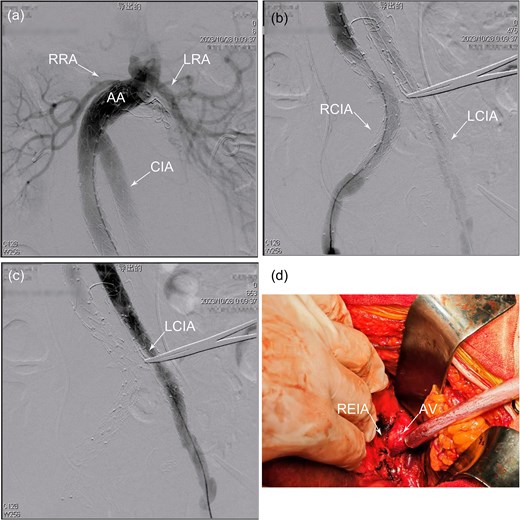

(a) Proximal angiography showed occlusion of the back-bleeding side branches leading to type II endoleak. (b) Distal angiography revealed an effective isolation of a type 1b endoleak in the right common iliac artery, but there was an absence of the right internal iliac artery. (c) After relining the graft with an additional branched iliac device, angiography confirmed the successful isolation of a type III endoleak, with no contrast leakage observed between the iliac branch and the main body of the stent graft. (d) No active bleeding was observed at the bilateral anastomoses or within the graft following the release of the aortic clamp. AV, artificial vessel; LCIA, left common iliac artery; LIB, left iliac branch; RCIA, right common iliac artery; REIA, right external iliac artery; RIB, right iliac branch.

Upon careful opening of the aneurysm sac, intraoperative findings revealed retrograde flow from the patent inferior mesenteric artery (IMA) and the median sacral artery (MSA), consistent with a T2EL. Additionally, active hemorrhage was observed at the left common iliac stent–graft component, suggestive of a type III endoleak (T3EL). The IMA and MSA were ligated using pledgeted prolene 3–0 sutures (OBB5694SH, Johnson & Johnson/Ethicon). A second Endurant II Stent Graft System (ETLW-16-16-C-93-EE, Medtronic) was deployed via a percutaneous approach from the left femoral artery to seal the EL. Completion angiography confirmed the successful elimination of all ELs and the patency of both EIAs (Fig. 2a and b); however, it also revealed occlusion of both IIAs (Fig. 2c). Given the pre-existing occlusion of left IIA, an end-to-side anastomosis was performed using an artificial vessel (F4008C, 8 mm × 40 cm, Bard Medical) to restore perfusion from the distal right EIA to the right IIA (Fig. 2d). Following clamp release, the right IIA demonstrated robust pulsatility. Finally, aneurysmorrhaphy was performed, and the abdominal incision was closed in layers.